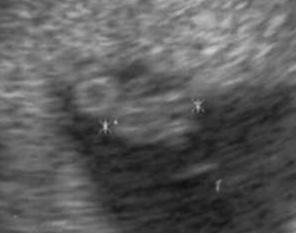

Kedden uh, tarkóredő mérés, meg minden, és akkor hivatalosan is megnyugodhatok végre. Legalábbis remélem. Elvégre 23 évesen vajmi kevés esélyem van a Down-kórra, ez miatt nem izgulok, és 2 hete is minden rendben volt, mikor nem bírtam tovább és elrohantam magán uh-ra…akkor most miért ne lenne?

Várom már nagyon, kiváncsi vagyok mennyit nőtt?! Jó lenne, ha esetleg olyan profi lenne a doki, meg úgy is feküdne a baby, hogy meg tudnák mondani, hogy mi van a lába között. Bár ilyen pici korban esélyesebb inkább csak a fiúkat észrevenni, úh akkor inkább nem akarom tudni.

Kisbabánk

Kisbabánk